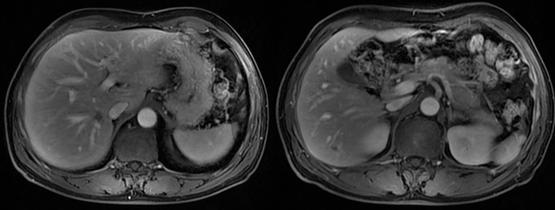

MR随访示病灶保持基本稳定(2020.2)

MR示肝脏转移较前有所增大(2020.11)